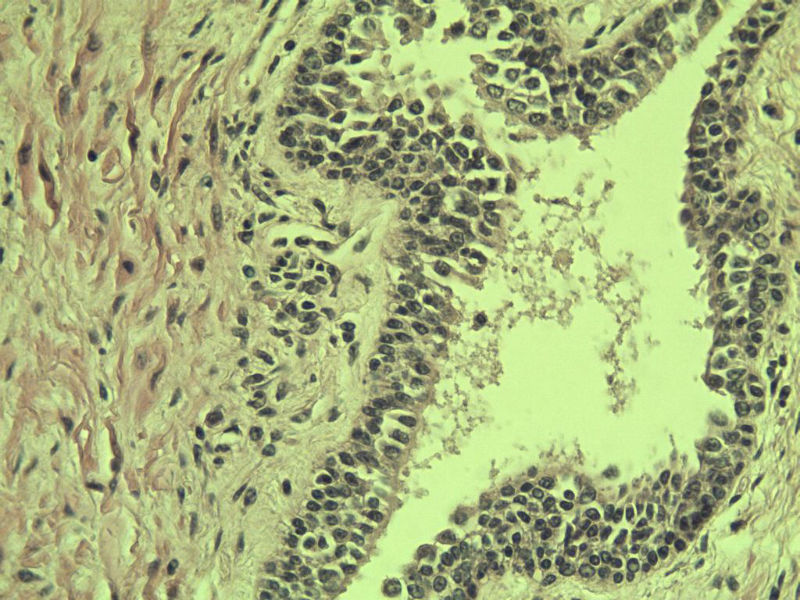

男 75岁 因排尿困难半年行前列腺切除术,体积 4 × 3 × 2.5 cm3,切面灰白,实性,质韧。请各位老师看看 有问题没? 谢谢了!

高级别上皮内瘤变,建议免疫组化:P63、34BE12、P504S

前列腺增生症伴鳞化

良性前列腺增生伴尿路上皮化生

前列腺增生伴尿路上皮鳞化及Brown巢形成,未见恶性。